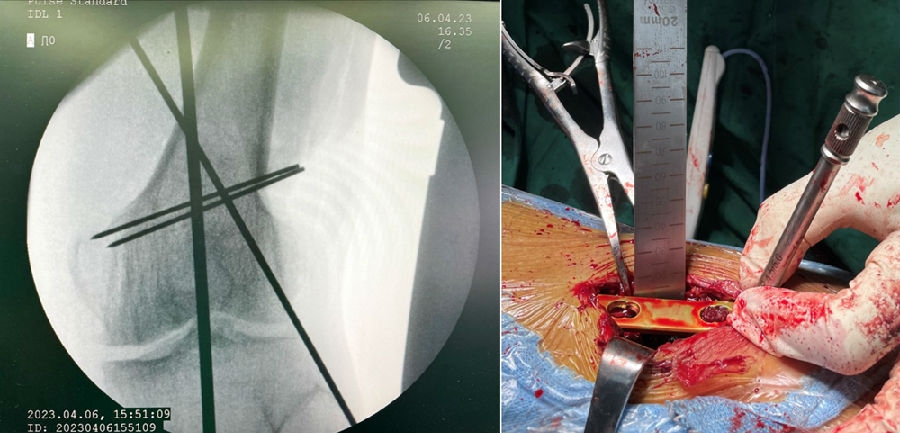

术后影像